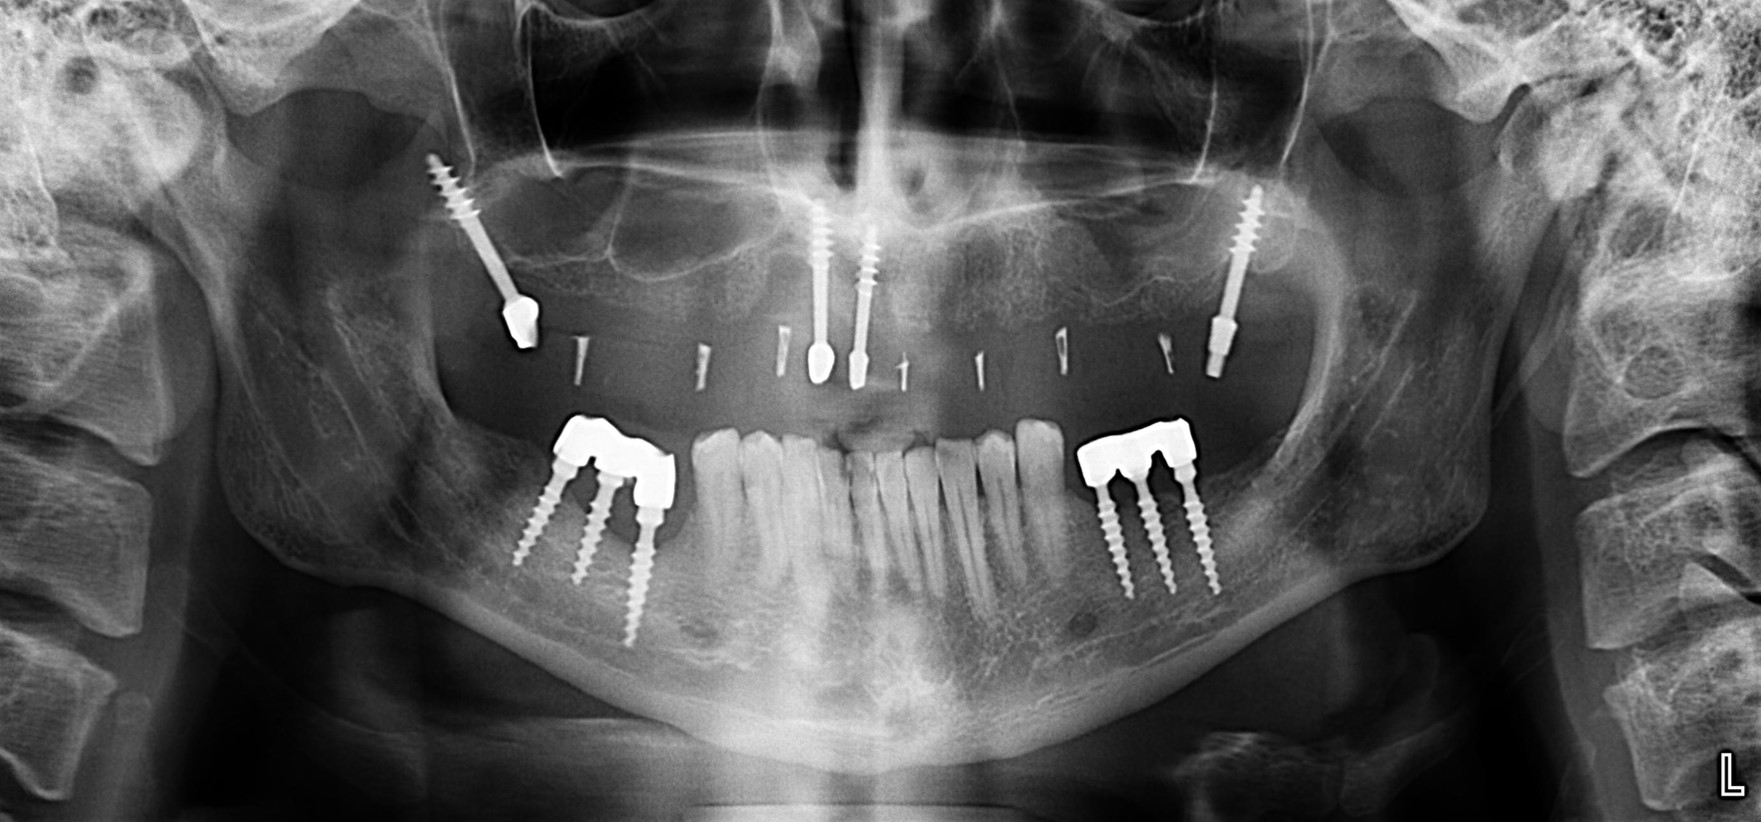

А теперь посмотрите снимок этого пациента:

Как вы считаете, что будет травматичнее и опаснее: установка шести имплантов такой формы или два простых синуслифтинга и шесть обычных имплантов?

К слову сказать, базальные импланты не интегрируются, а удерживаются, исключительно, за счет своей формы:

А это значит, что длительная функциональная нагрузка в таком объеме просто будет их медленно расшатывать. Особенно, если учесть, что их нагружают почти сразу после установки. И весьма большой протетической конструкцией.

И вот, у этой пациентки все импланты, а их, ни много, ни мало, восемь штук, подвижны: